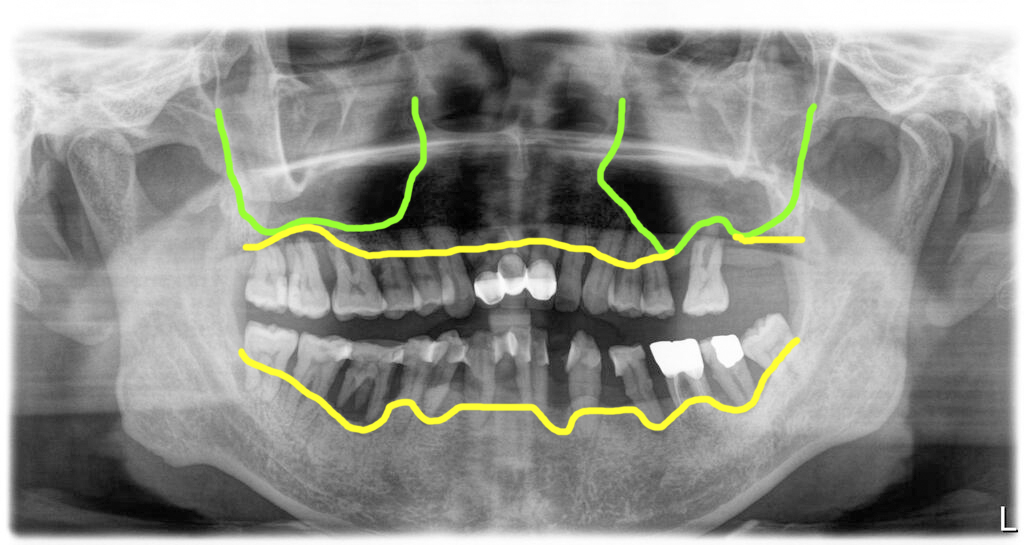

2년반 경과후 내원 치주염 상태 심해지고 일부치아는 자연 발치된 상태

그렇게 해서 환자는 약 2년 반이 지나서 다시 병원에 오셨어요. 그동안 치주염이 더 심해서 치아들이 많이 흔들려서 치아들을 서로 연결을 한 흔적이 보였습니다. 하지만 그렇게 연결한다고 다시 잇몸이 건강해지는 것은 아닙니다. 몇 개의 치아는 스스로 빠지기까지 한 상태였습니다.

결국 이제는 더이상 미룰 수 없다고 생각하시고 치료를 시작하기로 했습니다. 입 안 상태를 확인했을 때 2년 전에 살릴 수 있다고 판단한 치아들까지 모두 흔들리고 상태가 좋지 않아서 결국 모든 치아를 발치하기로 결정하고 전체임플란트 치료를 시작했습니다.